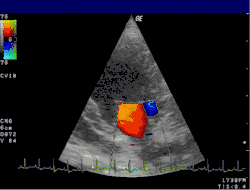

Transesophageal echocardiogram of mitral valve prolapse

An echocardiogram is commonly used to confirm the diagnosis of MR.[16] Color doppler flow on the transthoracic echocardiogram (TTE) will reveal a jet of blood flowing from the left ventricle into the left atrium during ventricular systole. Also, it may detect a dilated left atrium and ventricle and decreased left ventricular function.[6] A transesophageal echocardiogram can give clearer images if needed as the back of the heart can also be viewed.[17]